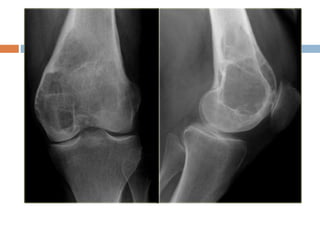

Xray

 Radiolucent area eccentrically at end of long

bone, bounded by sub-chondral plate

 Center has soap bubble appearance due to

ridging of surrounding bone

 Cortex is thin and ballooned

 Appearance of cystic lesion in mature bone

extending upto subchondral plate is

characterstic.